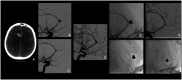

BackgroundData on off-label use of flow diverter for ruptured distal anterior cerebral artery aneurysms (rDACAAs) are limited. The purpose of the present study is to evaluate the efficacy and safety of flow diversion for rDACAAs in a large multicenter cohort.MethodsA retrospective observational study on consecutive patients who were treated with flow diversion for rDACAAs at 8 centers in 4 countries was performed. Primary outcome was the occlusion rate of the target aneurysm at the last radiological follow-up. Secondary outcomes included good clinical outcome, retreatment, technical success, procedure-related complications, radiological outcome of the covered branches and mortality rate.ResultsA total of 21 patients with 21 rDACAAs were treated between January 2017 and December 2024. Thirteen patients were women (61.9%) and the median age was 54 years (IQR 46-66). The most common etiology was saccular (71.4%), followed by dissecting (23.8%) and mycotic (4.8%). In all patients a single stent was successful deployed. Median imaging follow-up was 9 (7-12) months. At last follow-up adequate occlusion was 95.2%. Symptomatic thromboembolic or hemorrhagic complications occurred in 9.5% of patients. Seventeen patients (81%) had good clinical outcome (mRS 0-2) with mortality rate of 9.5%. In-stent stenosis occurred in one case that was conservatively managed without major concerns.ConclusionsFlow diversion is feasible as a potential treatment strategy for acutely ruptured aneurysms arising from distal anterior cerebral artery. Flow diverter may represent a valid option whenever other treatments are considered challenging or high risk.